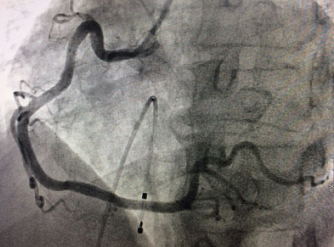

???我院成功開展市屬醫(yī)院首例冠狀動脈內(nèi)膜旋磨術???? 在心臟血管內(nèi)開“隧道”,用高速旋轉的鉆石磨頭將堵塞心臟血管的鈣化斑塊磨碎,以此打通血管進行冠心病的介入治療,這看起來像科幻電影里的場面,在我院實現(xiàn)。近日,我院完成了全市市屬醫(yī)院首例冠狀動脈內(nèi)膜旋磨手術,成功開通了血管,解除了患者長期存在的胸悶...